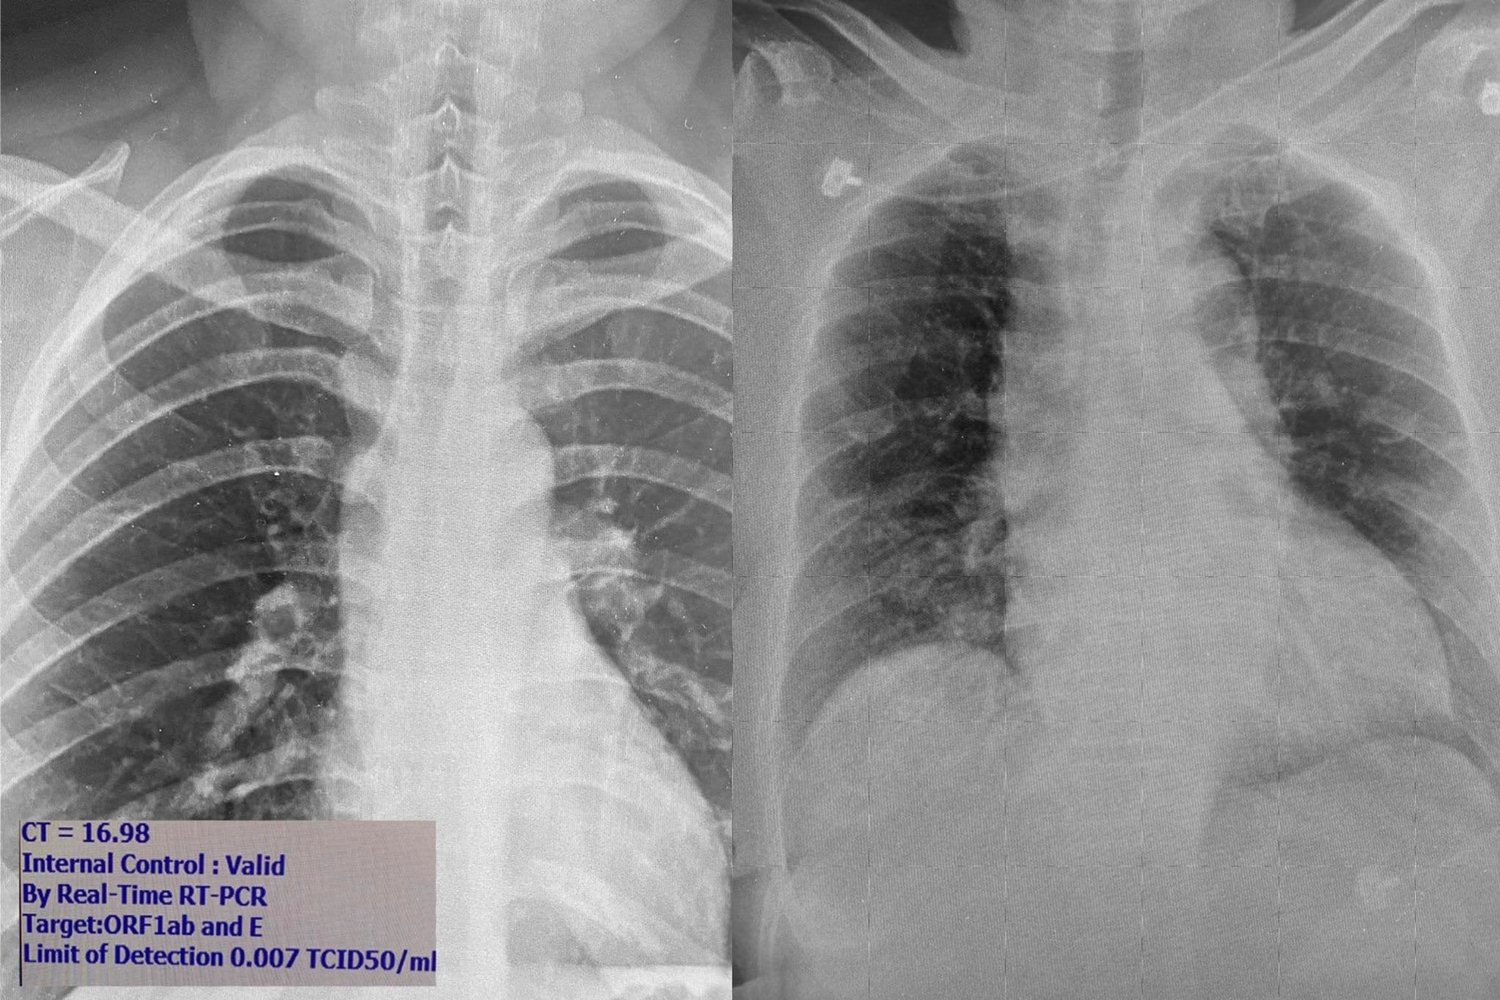

1. เชื้อแบ่งตัวได้ดีในจมูกและทางเดินหายใจ คนไม่มีอาการจะมีเชื้อในจมูกเยอะมากพร้อมที่จะแพร่กระจายเป็นวงกว้างเวลาไอ จามหรือพูด ในรูปภาพซ้าย ภาพถ่ายปอดผู้ที่ติดเชื้อที่ไม่มีอาการเลย เดินไปเดินมา ใช้ชีวิตเหมือนคนปกติ แต่เชื้อในจมูกค่า CT (cycle threshold) จากเครื่อง PCR บอกว่ามีปริมาณเชื้อในจมูกสูง มากเมื่อเทียบกับคนไข้ที่เคยเห็นในระลอกแรก ดังนั้นถ้าไม่ได้มาตรวจก็แพร่กระจายเชื้อคนอื่นได้อีกมาก

2. รูปขวา--เราเริ่มเห็นคนมีอาการไข้หวัดหรือปอดอักเสบมาที่โรงพยาบาล แต่ไม่ยอมบอกประวัติความเสี่ยงเพื่อปกปิดการเดินทาง แพทย์อาจไม่ได้ส่งตรวจหาโควิด เพราะคิดว่าเป็นปอดอักเสบจากเชื้ออื่นที่พบได้บ่อยกว่า